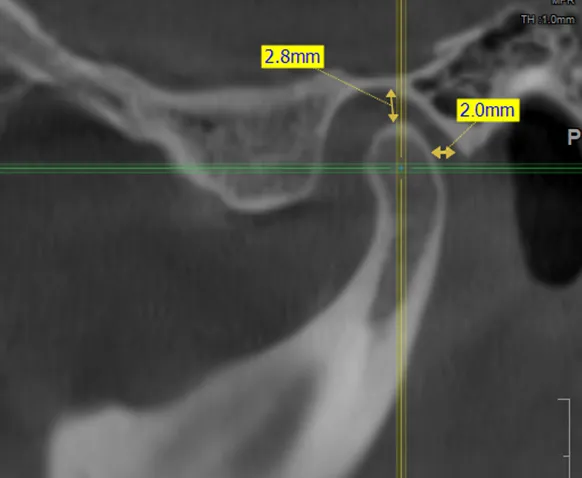

• компьютерная томография (КТ),